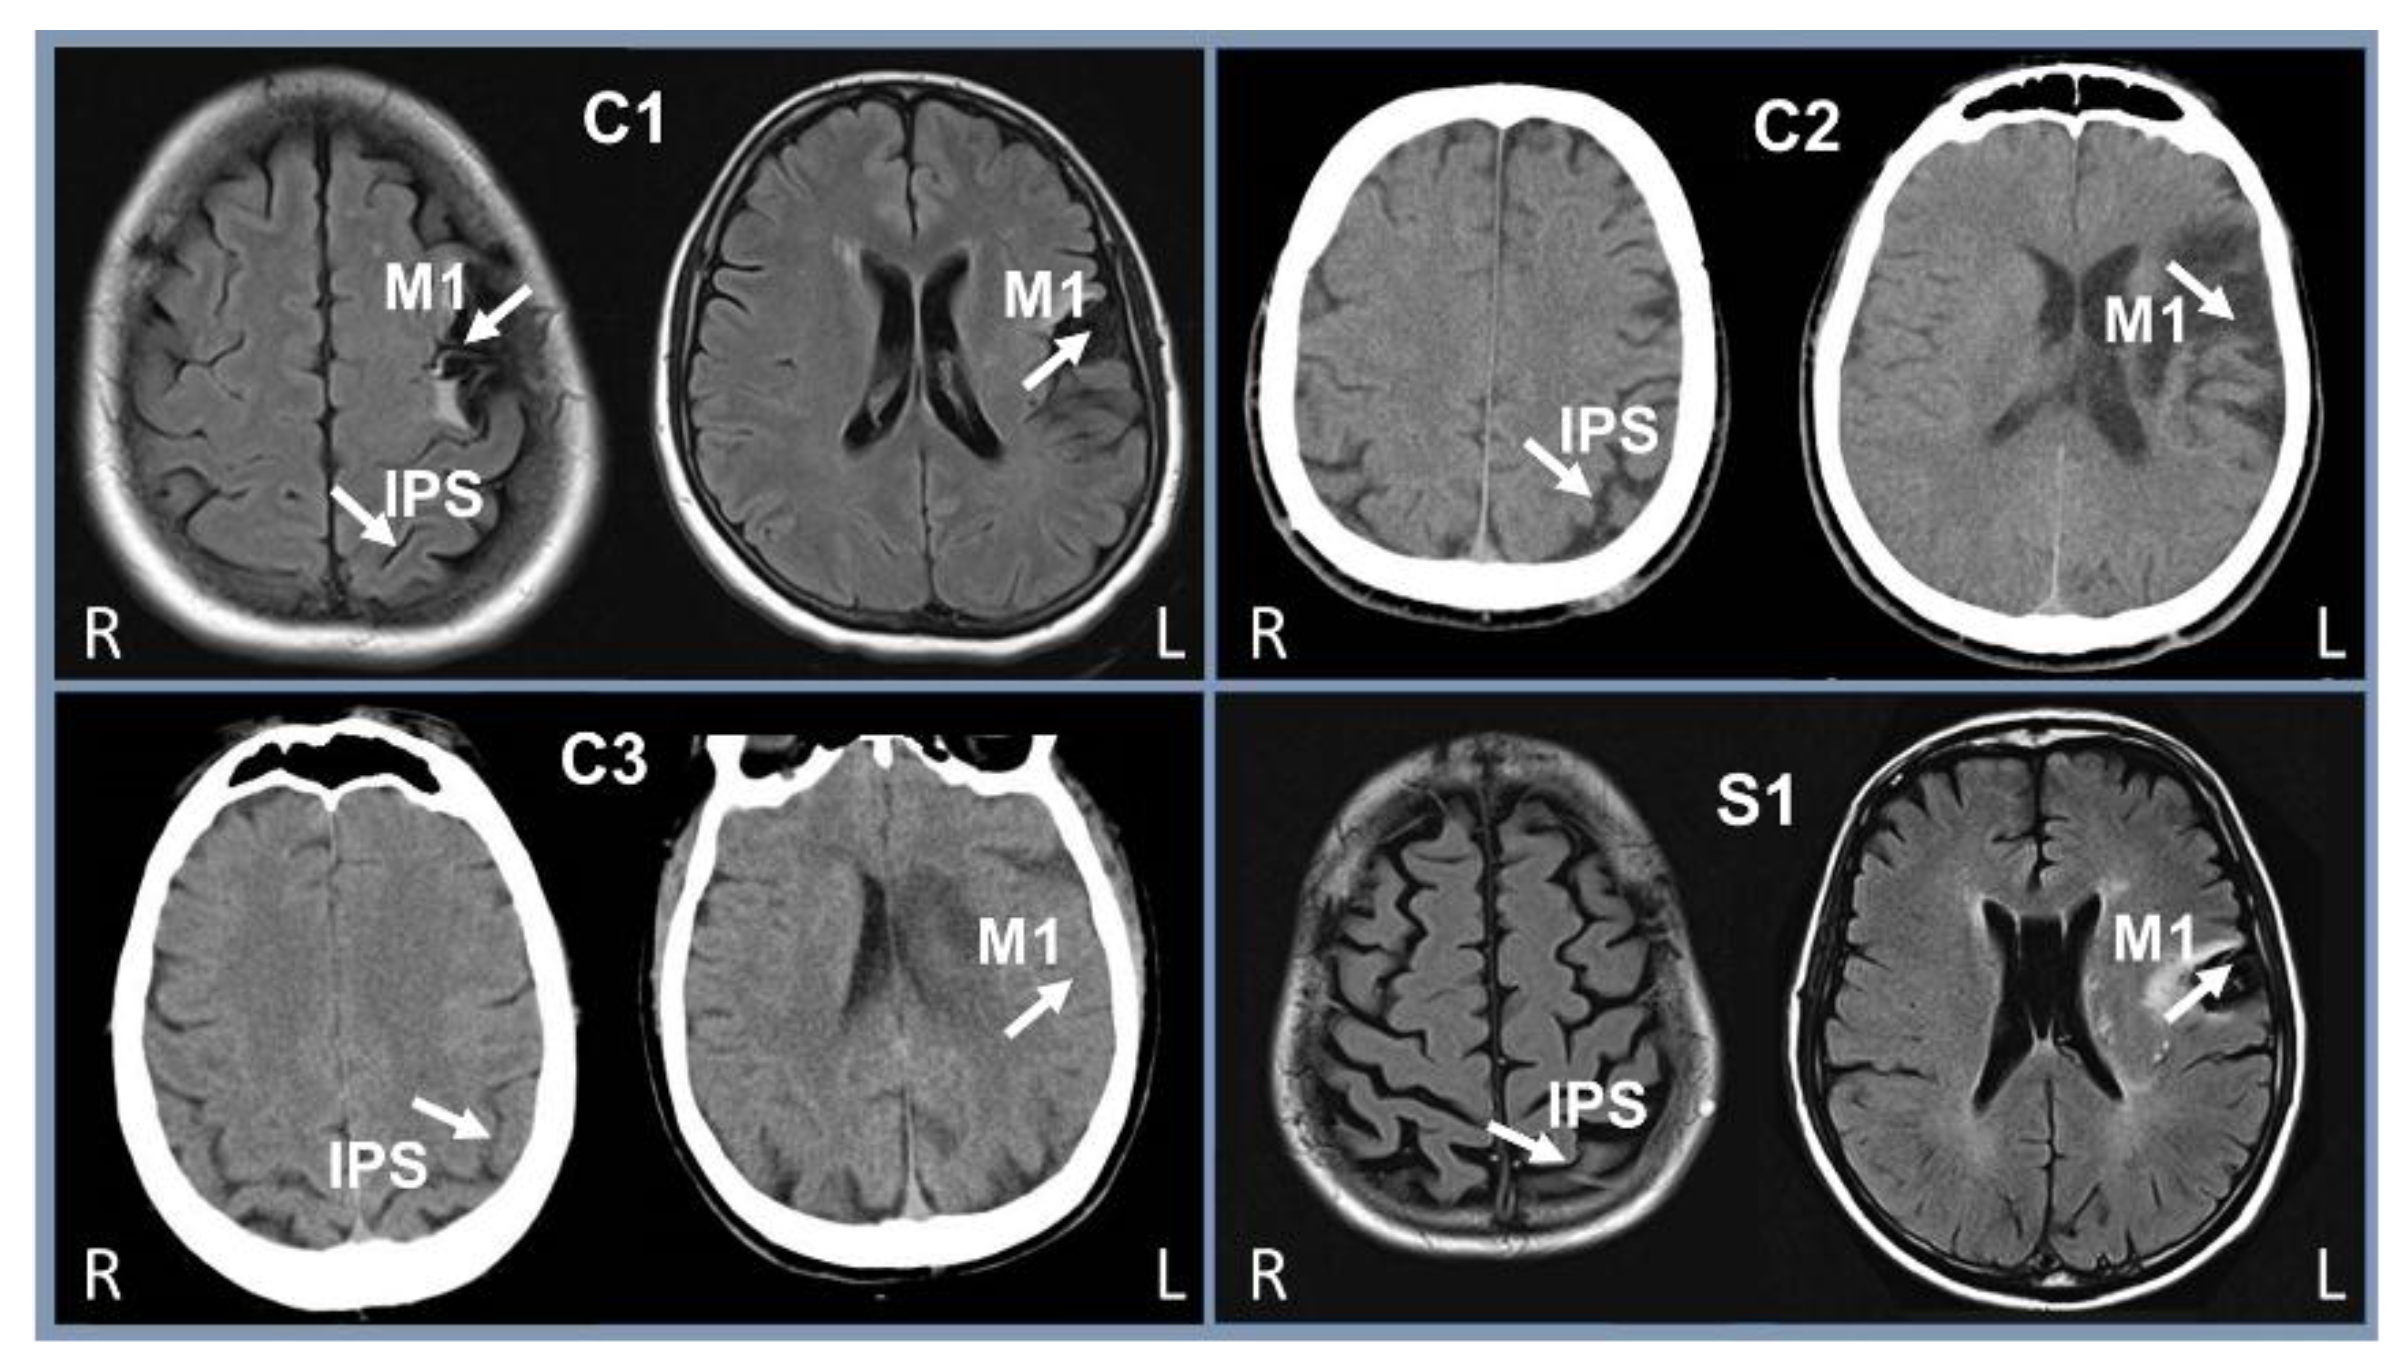

2.2. Subjects